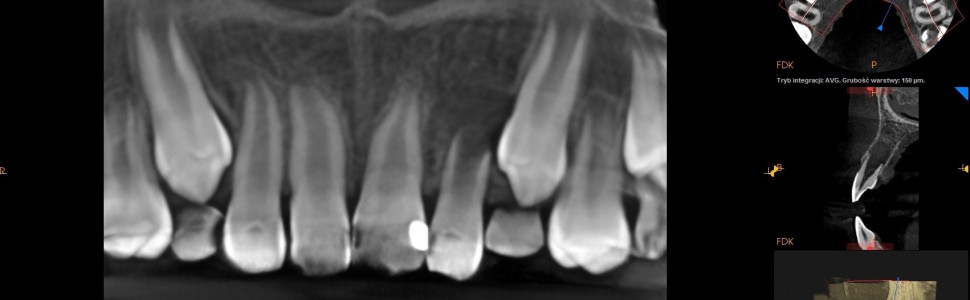

W pracy opisano leczenie endodontyczne zęba z bardzo szerokim, otwartym otworem wierzchołkowym. Na skutek urazu sprzed 2 lat doszło do wybicia zęba, który następnie został replantowany. Rozwinęła się martwica i zapalenie tkanek okołowierzchołkowych z zaburzeniami formowania wierzchołka korzenia. Do zamknięcia wierzchołka użyto preparatu MTA. W leczeniu wspomagano się badaniem CBCT oraz mikroskopem operacyjnym.

The study describes endodontic treatment of tooth with incomplete development of root. Due to trauma that had place two years, the tooth was avulsed, and then replanted. The necrosis and inflammation of periapical tissues with disturbance of apex formation has developed. To close the open apex MTA was used. To support the treatment CBCT and operative microscope were used.